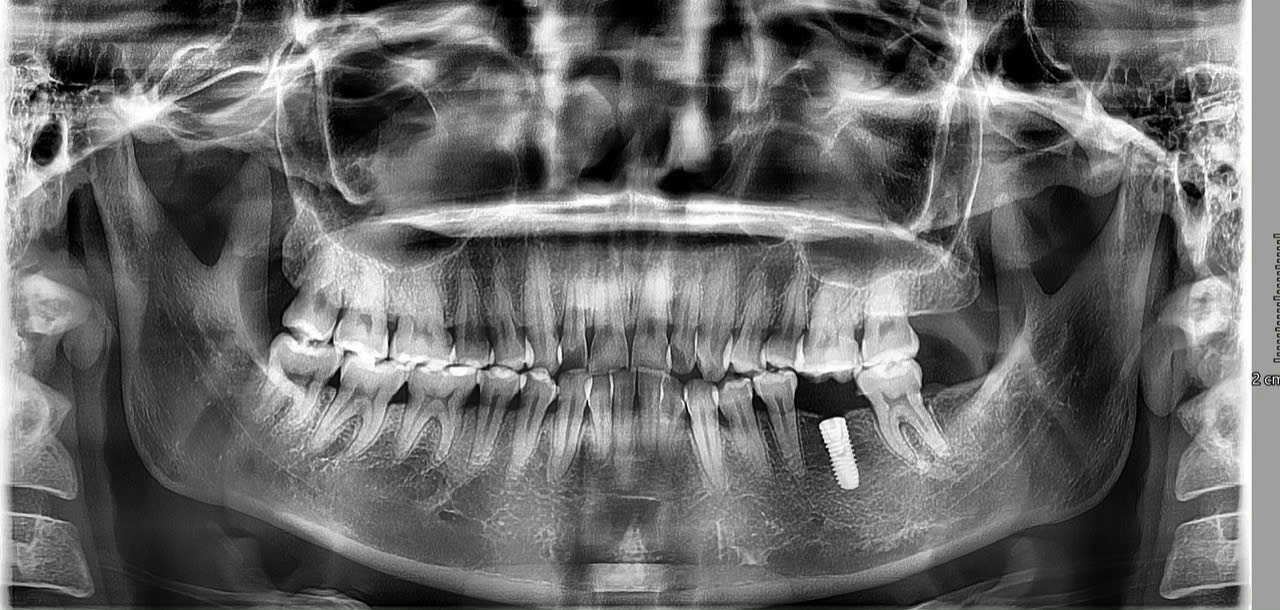

Hình 1: Mất răng - Nỗi lo lớn hơn bạn nghĩ

Bác sĩ kiểm tra tổng quát răng miệng, chụp phim X-quang 3D Conebeam để đánh giá mật độ và chất lượng xương hàm, từ đó tư vấn phương án điều trị phù hợp nhất.